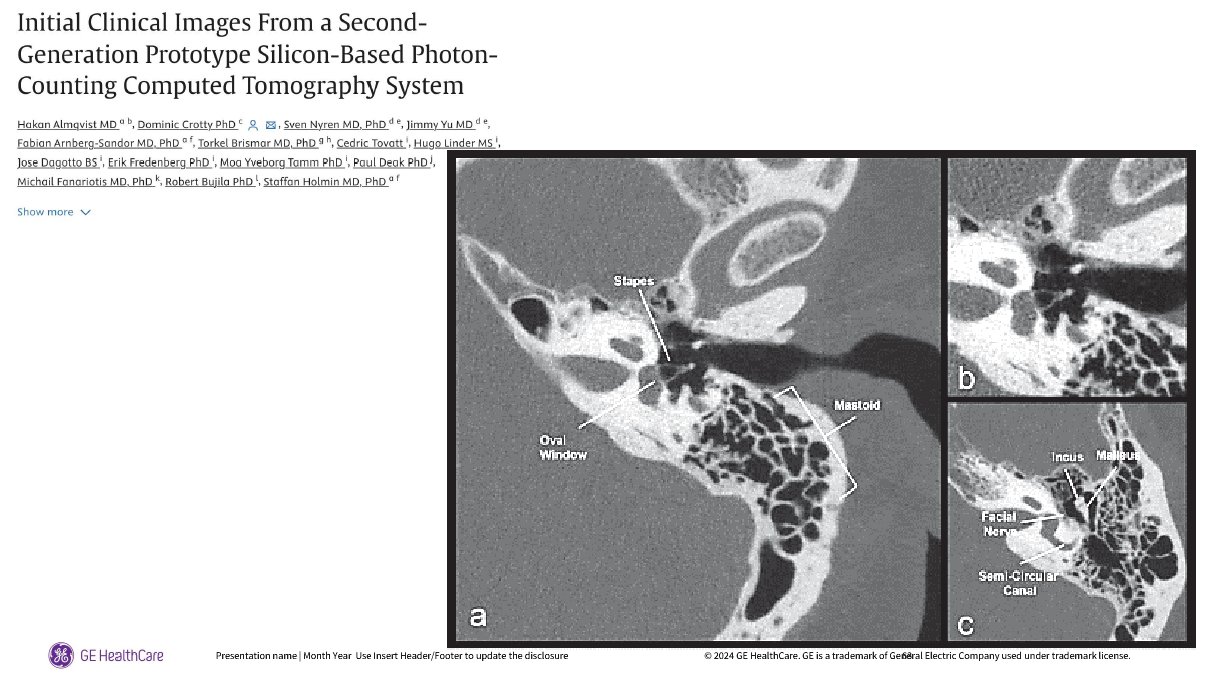

Des images d’oreilles internes remarquables, l’étrier et la chaine ossiculaire sont parfaitement détectés.